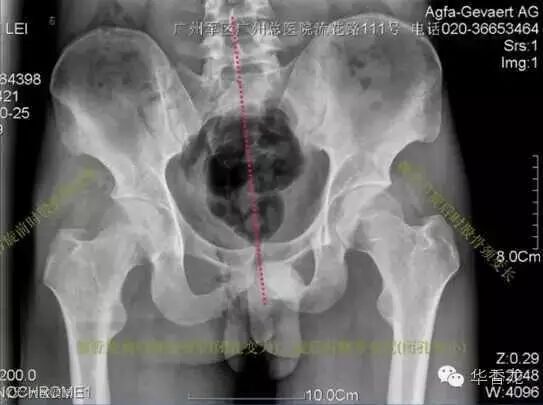

X线片

通过片子也能发现骨盆偏歪的问题。即使大家不懂医学,但看看骨盆下面两个像眼睛一样的圆洞洞,是不是不一样大,髋骨两边像耳朵一样的骨头是不是不一样大,骨头最上缘是不是不在一条直线上,片子可以清晰地显示出来。